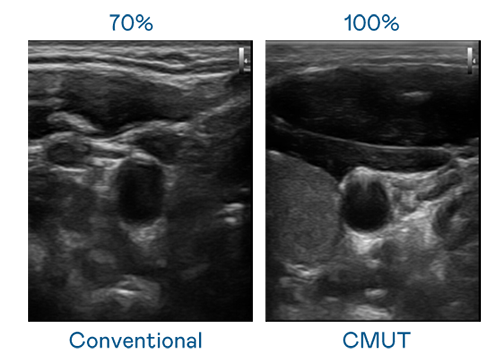

CMUT 技术是一种用电容式微机电元件来产生超音波讯号的技术。与传统 PZT 压电式技术相比,CMUT 频宽增加 30%,更宽频的超音波讯号让影像解析度大幅提升,是实现高影像品质医疗超音波扫描、促进精准医疗发展的关键技术。

超音波影像的解析度高低,首先取决于探头能发出的讯号频宽。DB真人 CMUT 可提供高清晰的超音波讯号,提供高频宽、高灵敏度、影像纹理细节更高的超音波影像,协助医护人员缩短影像判读时间及利用精准的医疗影像进行诊断。